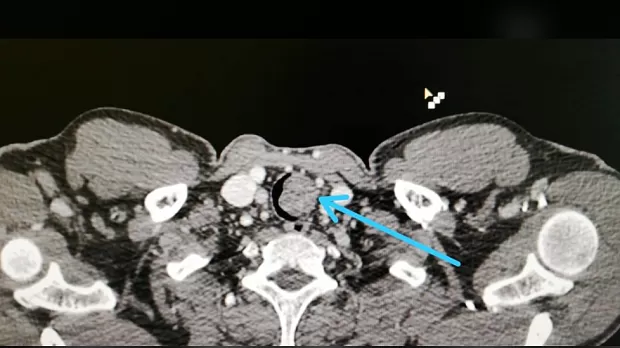

Пациент Р. 1988 г.р., госпитализирован в клинику для дообследования и оперативного лечения с диагнозом: образование в/3 трахеи. На амбулаторном этапе при бронхоскопии выявлено образование в/3 трахеи, биопсия не взята. После госпитализации в нашу клинику проведено КТ, на томографии имеется образование размерами 2.4х2.3 см, с ножкой 13 мм, с плотностью до 40 ед, имеется инвазия в области ножки в подслизистый слой на 6 мм, рядом увеличенный лимфоузел.